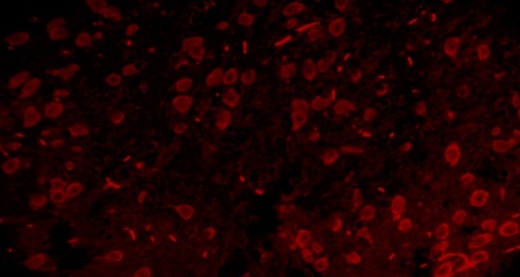

Immunoflourescence

5 µM-thick paraffin sections through matched coronal levels of the SNpc and ST were processed as described above and non-specific binding was blocked by 1 h incubation in 1.5% BSA. Sections were incubated with primary antibody, mouse anti-NeuN (1:100) for one hour and then subsequently incubated with secondary antibody, TRITC conjugated goat anti-mouse IgG (1:20) for half an hour at room temperature. The number of positive cells in SNpc and ST was counted under x400 magnification with image analysis software (Motic DMB1–2MP, China). Percentage immunopositive cells were calculated as: (Number of immunopositive cells/mm2)/(Total number of cells/mm2) X 100.

TEL increased NeuN expressions in MPTP intoxicated mice brain

SNpc and ST regions of MPTP mice brain showed a significant decrease in % NeuN immunopositive cells [F (4,10) = 274.1, p<0.01 and F (4,10) = 86.24, p<0.01, respectively] when compared to the vehicle treated mice. TEL (3 and 10 mg/kg) significantly (p<0.01) increased % NeuN immunopositive cells in both the regions in comparison to MPTP mice (fig. 4).

Fig. 4: Effect of TEL on % NeuN immunopositive cells in MPTP intoxicated mice brain. Pictures represent NeuN immunopositive cells of (A) SNPc and (B) ST brain regions X 400 magnification. (1) Normal control, (2) MPTP induced mice brain, (3) TEL (3 mg/kg b. wt.) administered MPTP mice brain, (4) TEL (10 mg/kg b. wt.) administered MPTP mice brain and (5) TEL (10 mg/kg b. wt.) administered normal mice brain. (C) Values were expressed in mean±SEM, n=4 animals/group, statistical analysis was performed using one way ANOVA followed by Tukey’s multiple comparison test, ## indicates p value<0.01 Vs group I, ** indicates p value<0.01 Vs group II